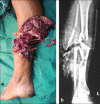

The decision to amputate or salvage a severely injured limb can be very challenging to the trauma surgeon. A misjudgment will result in either an unnecessary amputation of a valuable limb or a secondary amputation after failed salvage. Numerous scores have been proposed to provide guidelines to the treating surgeon, the notable of which are Mangled extremity severity score (MESS); the predictive salvage index (PSI); the Limb Salvage Index (LSI); the Nerve Injury, Ischemia, Soft tissue injury, Skeletal injury, Shock and Age of patient (NISSSA) score; and the Hannover fracture scale-97 (HFS-97). These scores have all been designed to evaluate limbs with combined orthopaedic and vascular injuries and have a poor sensitivity and specificity in evaluating IIIB injuries. Recently the Ganga Hospital Score (GHS) has been proposed which is specifically designed to evaluate a IIIB injury. Another notable feature of GHS is that it offers guidelines in the choice of the appropriate reconstruction protocol. The basis of the commonly used scores with their utility have been discussed in this paper.